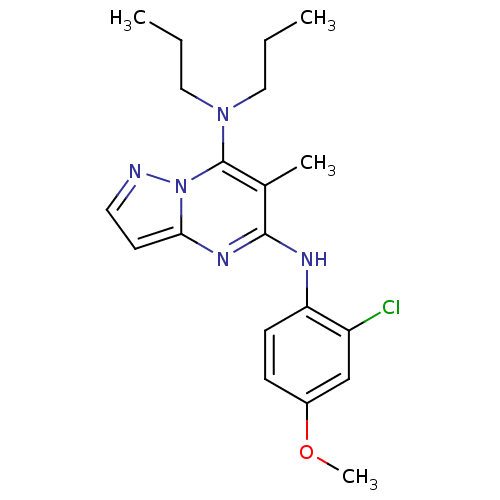

TargetCorticotropin-releasing factor receptor 1(Homo sapiens (Human))

Dupont Pharmaceuticals

Curated by ChEMBL

Dupont Pharmaceuticals

Curated by ChEMBL

Affinity DataEC50: 0.600nMAssay Description:Antagonist activity at human CRF1 receptor expressed in CHO-K1 cells assessed as CRF-stimulated cAMP accumulation by enzyme immunoassayMore data for this Ligand-Target Pair